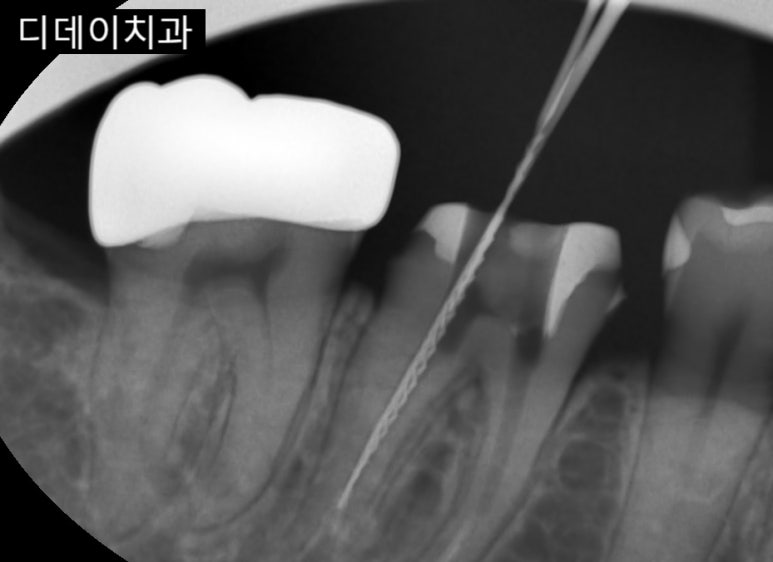

신경치료 진행중인 모습을 가까이서 촬영한 사진

충치가 깊어져 신경까지 침범하거나,

아직 신경까지는 침범하지 않았지만 썩은 부분과 함께 치아 일부분을 제거할 때

신경이 노출되어 자극받을 가능성이 있다면 신경치료 가능성에 대해서도 생각해 봐야 합니다.

이미 충치치료를 받았던 치아인데 계속 통증이 있거나 증상이 호전되지 않는 경우도 그렇고요.